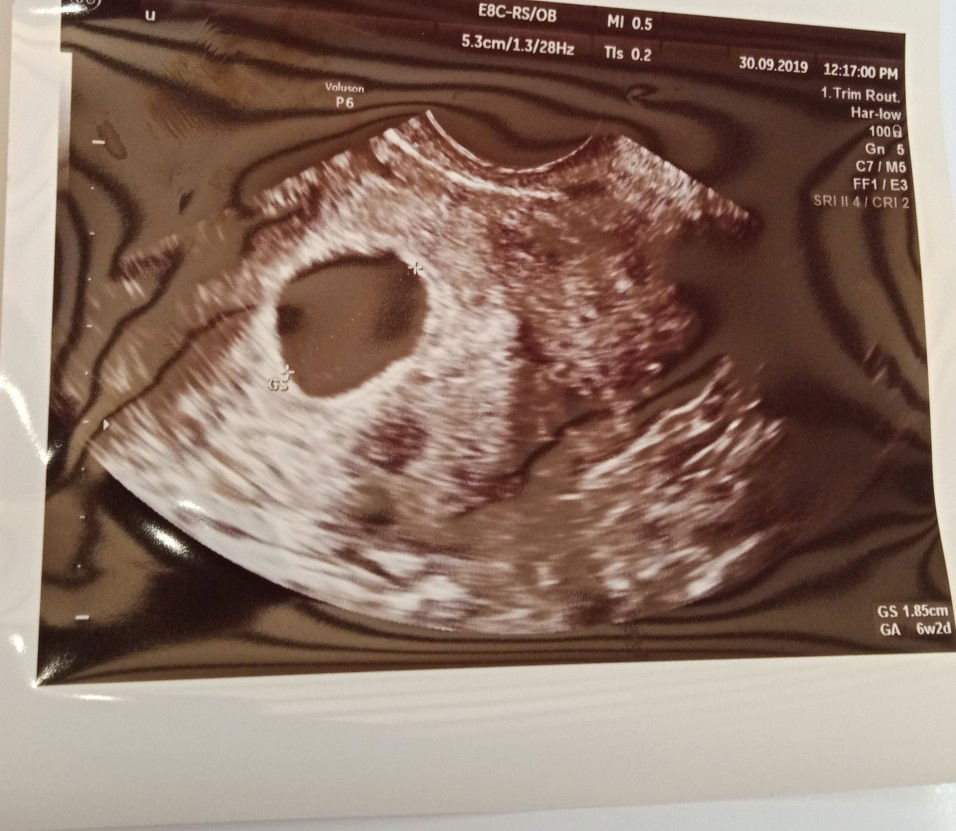

Usia Kandungan Tak Sama Dengan Scan

Assalamualaikum..hai mommies! Saya ibu kepada 3 org anak. Dan skarang saya disahkan mengndung anak ke 4. Kalau ikut tarikh last period saya, usia kndungan dah 9w++.. Khamis lepas saya ke KK untuk appoinment scan. Tapi malangnya, doctor bgtau fetus takde! Hanya kantung sahaja. Dia bg tarikh lagi dua minggu untuk datang scan. Dalam masa yg sama, sy ada spot bleeding.. tak banyak smpai berketul, mcm lendir lendir coklat. Tp doktor sarankan kalau ada lagi bleeding terus ke hospital. Harini bleeding tu makin byk. Tapi still xde yg berketul. Cuma browniesh. Tapi byk. Skali lagi dekat hospital ni, doktor scan ikut bawah. Kantung kosong. Kt scan tunjuk baru 6w. Walaupun dh anak ke4, tp saya takde pengalaman yg cmni. Jarak dengan anak ketiga 5tahun. Umur pun dah menginjak 37tahun. sy sangat pasti dengan tarikh period sbb period sy regular, dan sy tanda di kalender setiap bulan. Ada yang situasi sama mcm saya? Tak nk fikir, tapi sikit sebanyak terganggu juga. Ye la, fikir xde pun baby kt dlm..huhu..nak tunggu lg dua minggu mcm2 dh fikir??